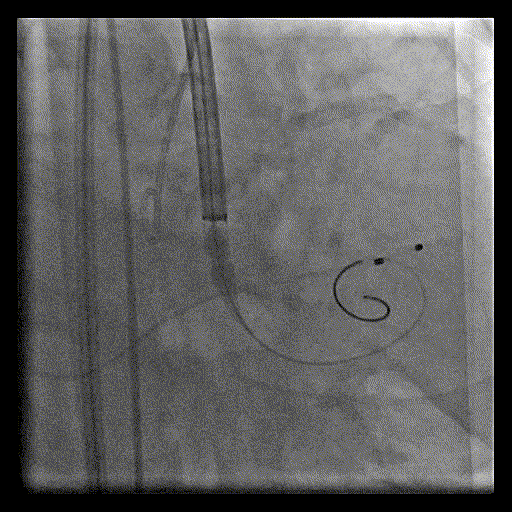

初始释放位置造影

释放至80%

造影确认深度及冠脉灌注情况